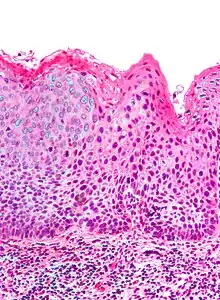

Micrograph of (classic) vulvar intraepithelial neoplasia III. H&E stain.

Medically speaking, the term denotes a squamous intraepithelial lesion of the vulva that shows dysplasia with varying degrees of atypia. The epithelial basement membrane is intact and the lesion is thus not invasive but has invasive potential.